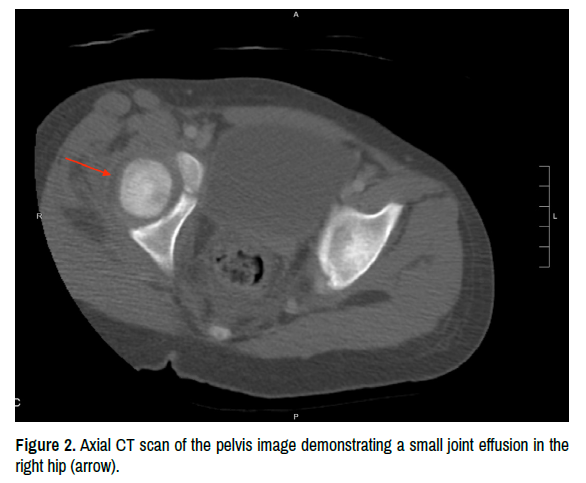

She was admitted to the pediatric floor for monitoring and was started on Intravenous (IV) ceftriaxone and metronidazole. Blood cultures at this time were positive for Group A Streptococcus. A Computed Tomography (CT) scan of her abdomen and pelvis was obtained with IV and PO contrast. It demonstrated a normal-appearing appendix, moderate wall thickening of the terminal ileum, and asymmetric hypertrophy of the right psoas and iliacus muscle with adjacent free fluid in the right hemipelvis (Figure 1). A small joint effusion in the right hip was noted but there were no other osseous abnormalities (Figure 2). General surgery was consulted for further evaluation and recommended transfer to a pediatric surgical specialty center.

clinical-case-reports-demonstrating

Figure 2. Axial CT scan of the pelvis image demonstrating a small joint effusion in the right hip (arrow).